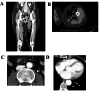

Gas gangrene is a rare presentation of a necrotizing fasciitis, caused by Clostridium perfringens, C. septicum and other clostridial species. With its rapid progression it is a potentially life-threatening infection, that poses as a challenge in the clinical management requiring an interdisciplinary approach.Here we present a 62-year-old woman, who developed neutropenic fever while undergoing chemotherapy for triple negative breast cancer. She presented with a high fever, reporting little pain in her left thigh accompanied by redness and induration locally. Subsequently the patient developed pain and redness of the back of the left hand. The initial findings suggested cellulitis and immediate empiric treatment with intravenous meropenem was started. Despite the antibiotic treatment the patient rapidly developed septic shock along with progression of the local infection. Emergency surgical debridement revealed extensive necrosis of the soft tissues including extensive myonecrosis of the thigh. On the left hand an extensive debridement was performed, the left lower limb could not be preserved and exarticulation of the left hip was required. Microbiologically C. septicum was isolated in different samples, confirming gas gangrene. As there was no local entry portal on the skin, hematogenous seeding from intestinal translocation in this neutropenic patient was suspected. The empiric antibiotic treatment was tailored to intravenous penicillin and complemented with clindamycin for toxin inhibition. Following radical debridement and antibiotic treatment, the patient could be stabilized. After repetitive debridement wound closure was achieved and the patient was discharged for rehabilitation. Antibiotic treatment was continued for four weeks.This rare case of gas gangrene in a neutropenic patient shows the complexity in the diagnostic and therapeutic management of necrotizing soft tissue infections in immunocompromised patients. It particularly highlights the importance of an interdisciplinary management with fast recognition of the disease and rapid, if needed radical, surgical debridement as well as tailored antibiotic treatment for a successful outcome.